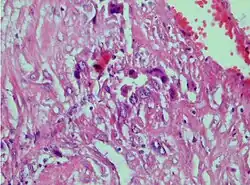

| Photomicrograph showing proliferating intermediate trophoblast with scarce cytotophoblastic and syncytiotrophoblastic elements | |

A placental site trophoblastic tumor is a monophasic neoplasm of the implantation site intermediate trophoblast, and usually a benign lesion, which comprises less than 2% of all gestational trophoblastic proliferations. Preceding conditions include molar pregnancy (5%). Compared to choriocarcinoma or invasive mole, hemorrhage is less conspicuous and serum β-HCG level is low, making early diagnosis difficult.